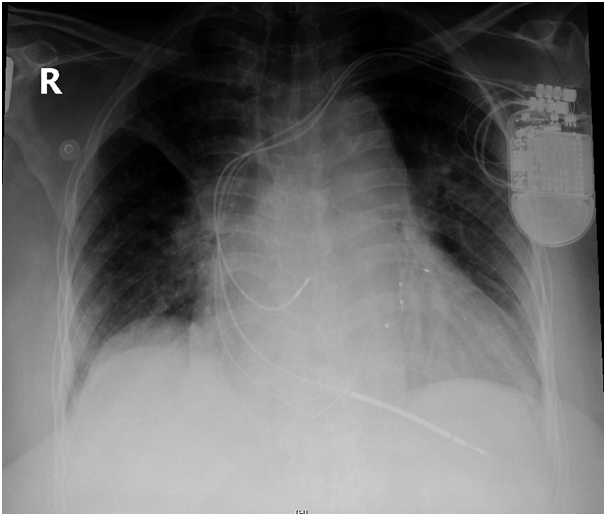

We were asked to see the patient, we reviewed her previous CXR post CRTD implantation and was (Figure 1) reviewed her procedure note which advocated the difficulty in securing LV lead deeply through lateral vein of the heart due to significant branch stenosis. The lead was then implanted in the posterolateral CS branch. Then, we requested a new CXR which showed the device slightly lower than implant position and displacement of LV lead higher in SVC (Figure 2).

Figure 2 The device slightly lower than implant position and displacement of LV lead higher in SVC.